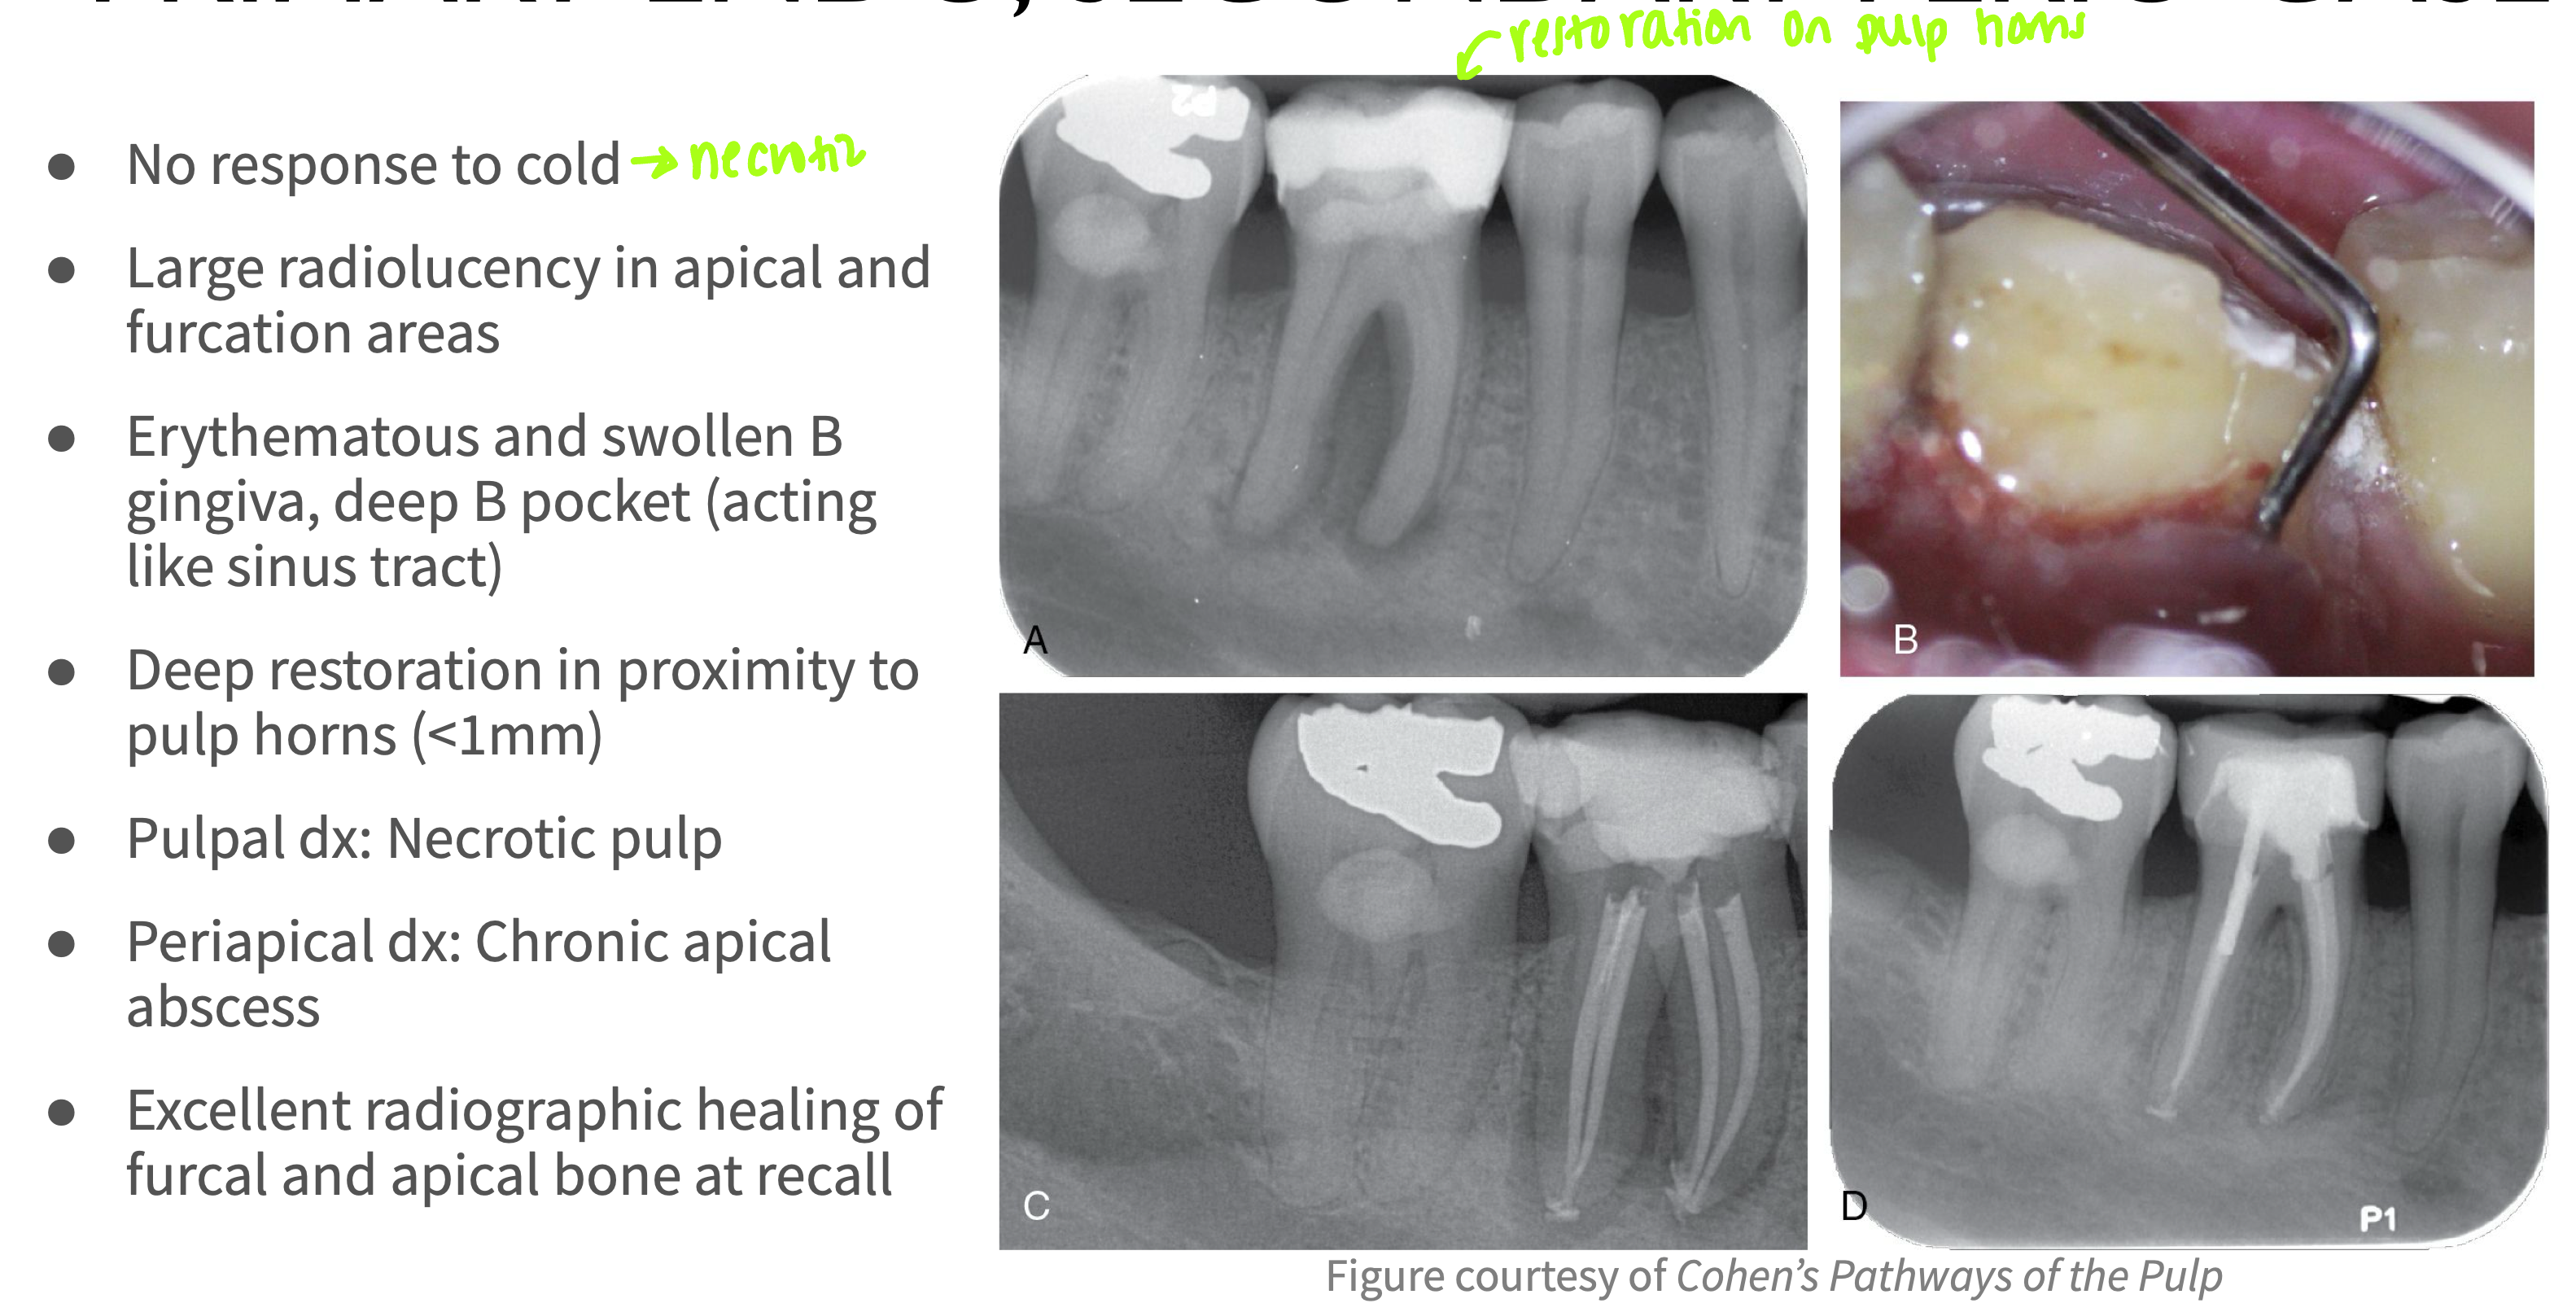

What type of lesion?

- No response to cold

- No pain on percussion or palpation

- Distal bone loss and deep pocket (independent of the PARL)

- Pulpal dx: Necrotic pulp

- Periapical dx: Asymptomatic apical periodontitis

Concomitant lesion